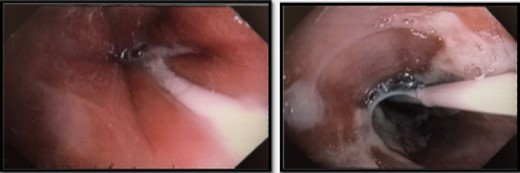

Interval gastroscopy in 2 weeks showed healing mucosal ischemia with slough from 27–30 cm (Fig. 3). Clear fluids were commenced and gradually upgraded to normal diet. Follow-up CT showed no contrast extravasation within posterior mediastinum (Fig. 4) and gastroscopy in 8 weeks showed healed esophagus.

Healing mucosal ischemia from upper, mid and distal esophagus.